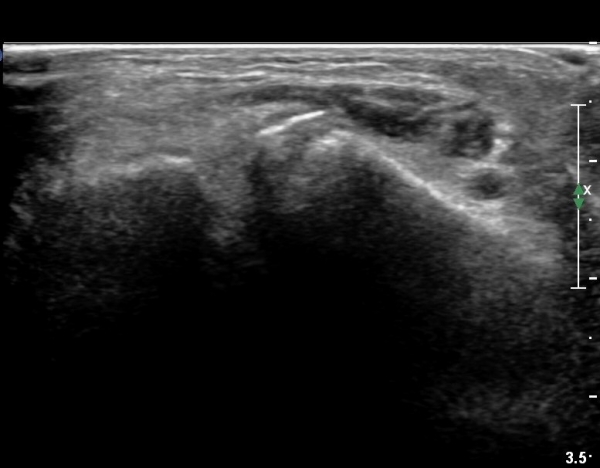

ÃÊÀ½ÆÄ °Ë»ç

CT : avulsion fracture of distal tibia at distal tibiofibulat ligament insertion.